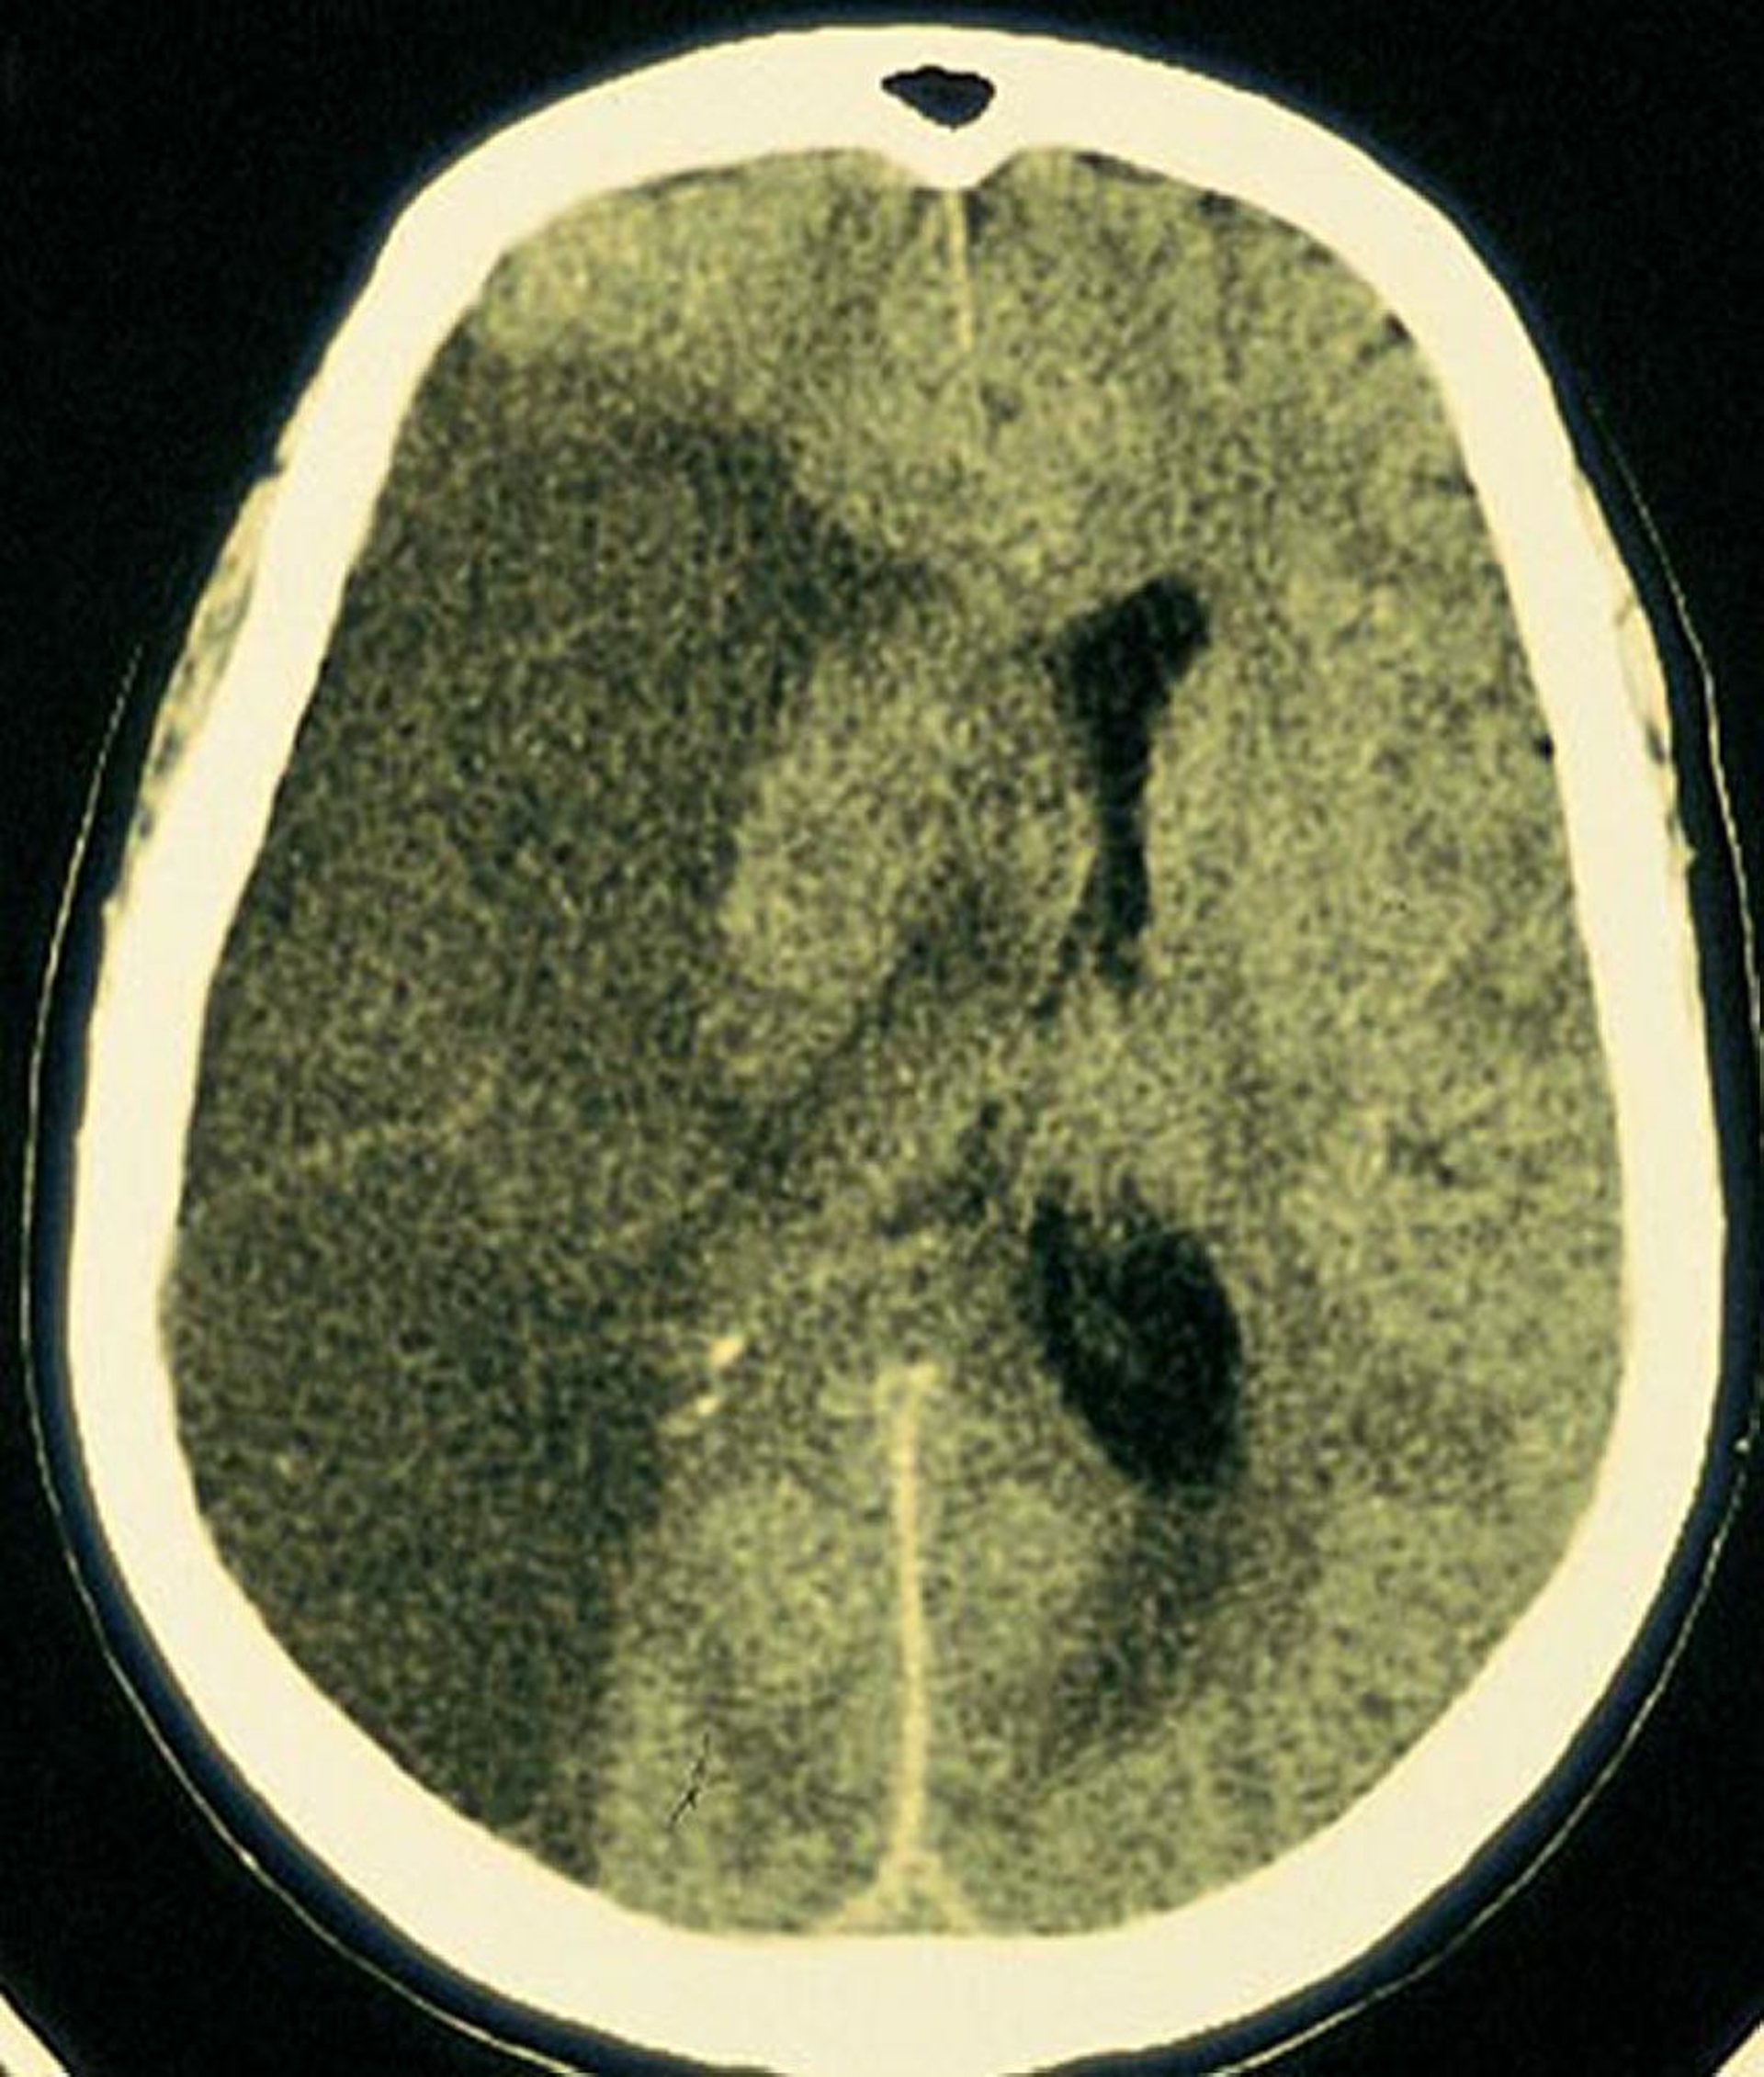

Nhồi máu động mạch não giữa

Quan sát thấy nhồi máu vùng sáng rộng ở vùng não được cấp máu bởi động mạch não giữa bên phải.

Được sự cho phép của nhà xuất bản. Từ Furie K, và cộng sự: Cerebrovascular disease. Trong Atlas of Clinical Neurology. Biên tập bởi RN Rosenberg. Philadelphia, Current Medicine, 2002.